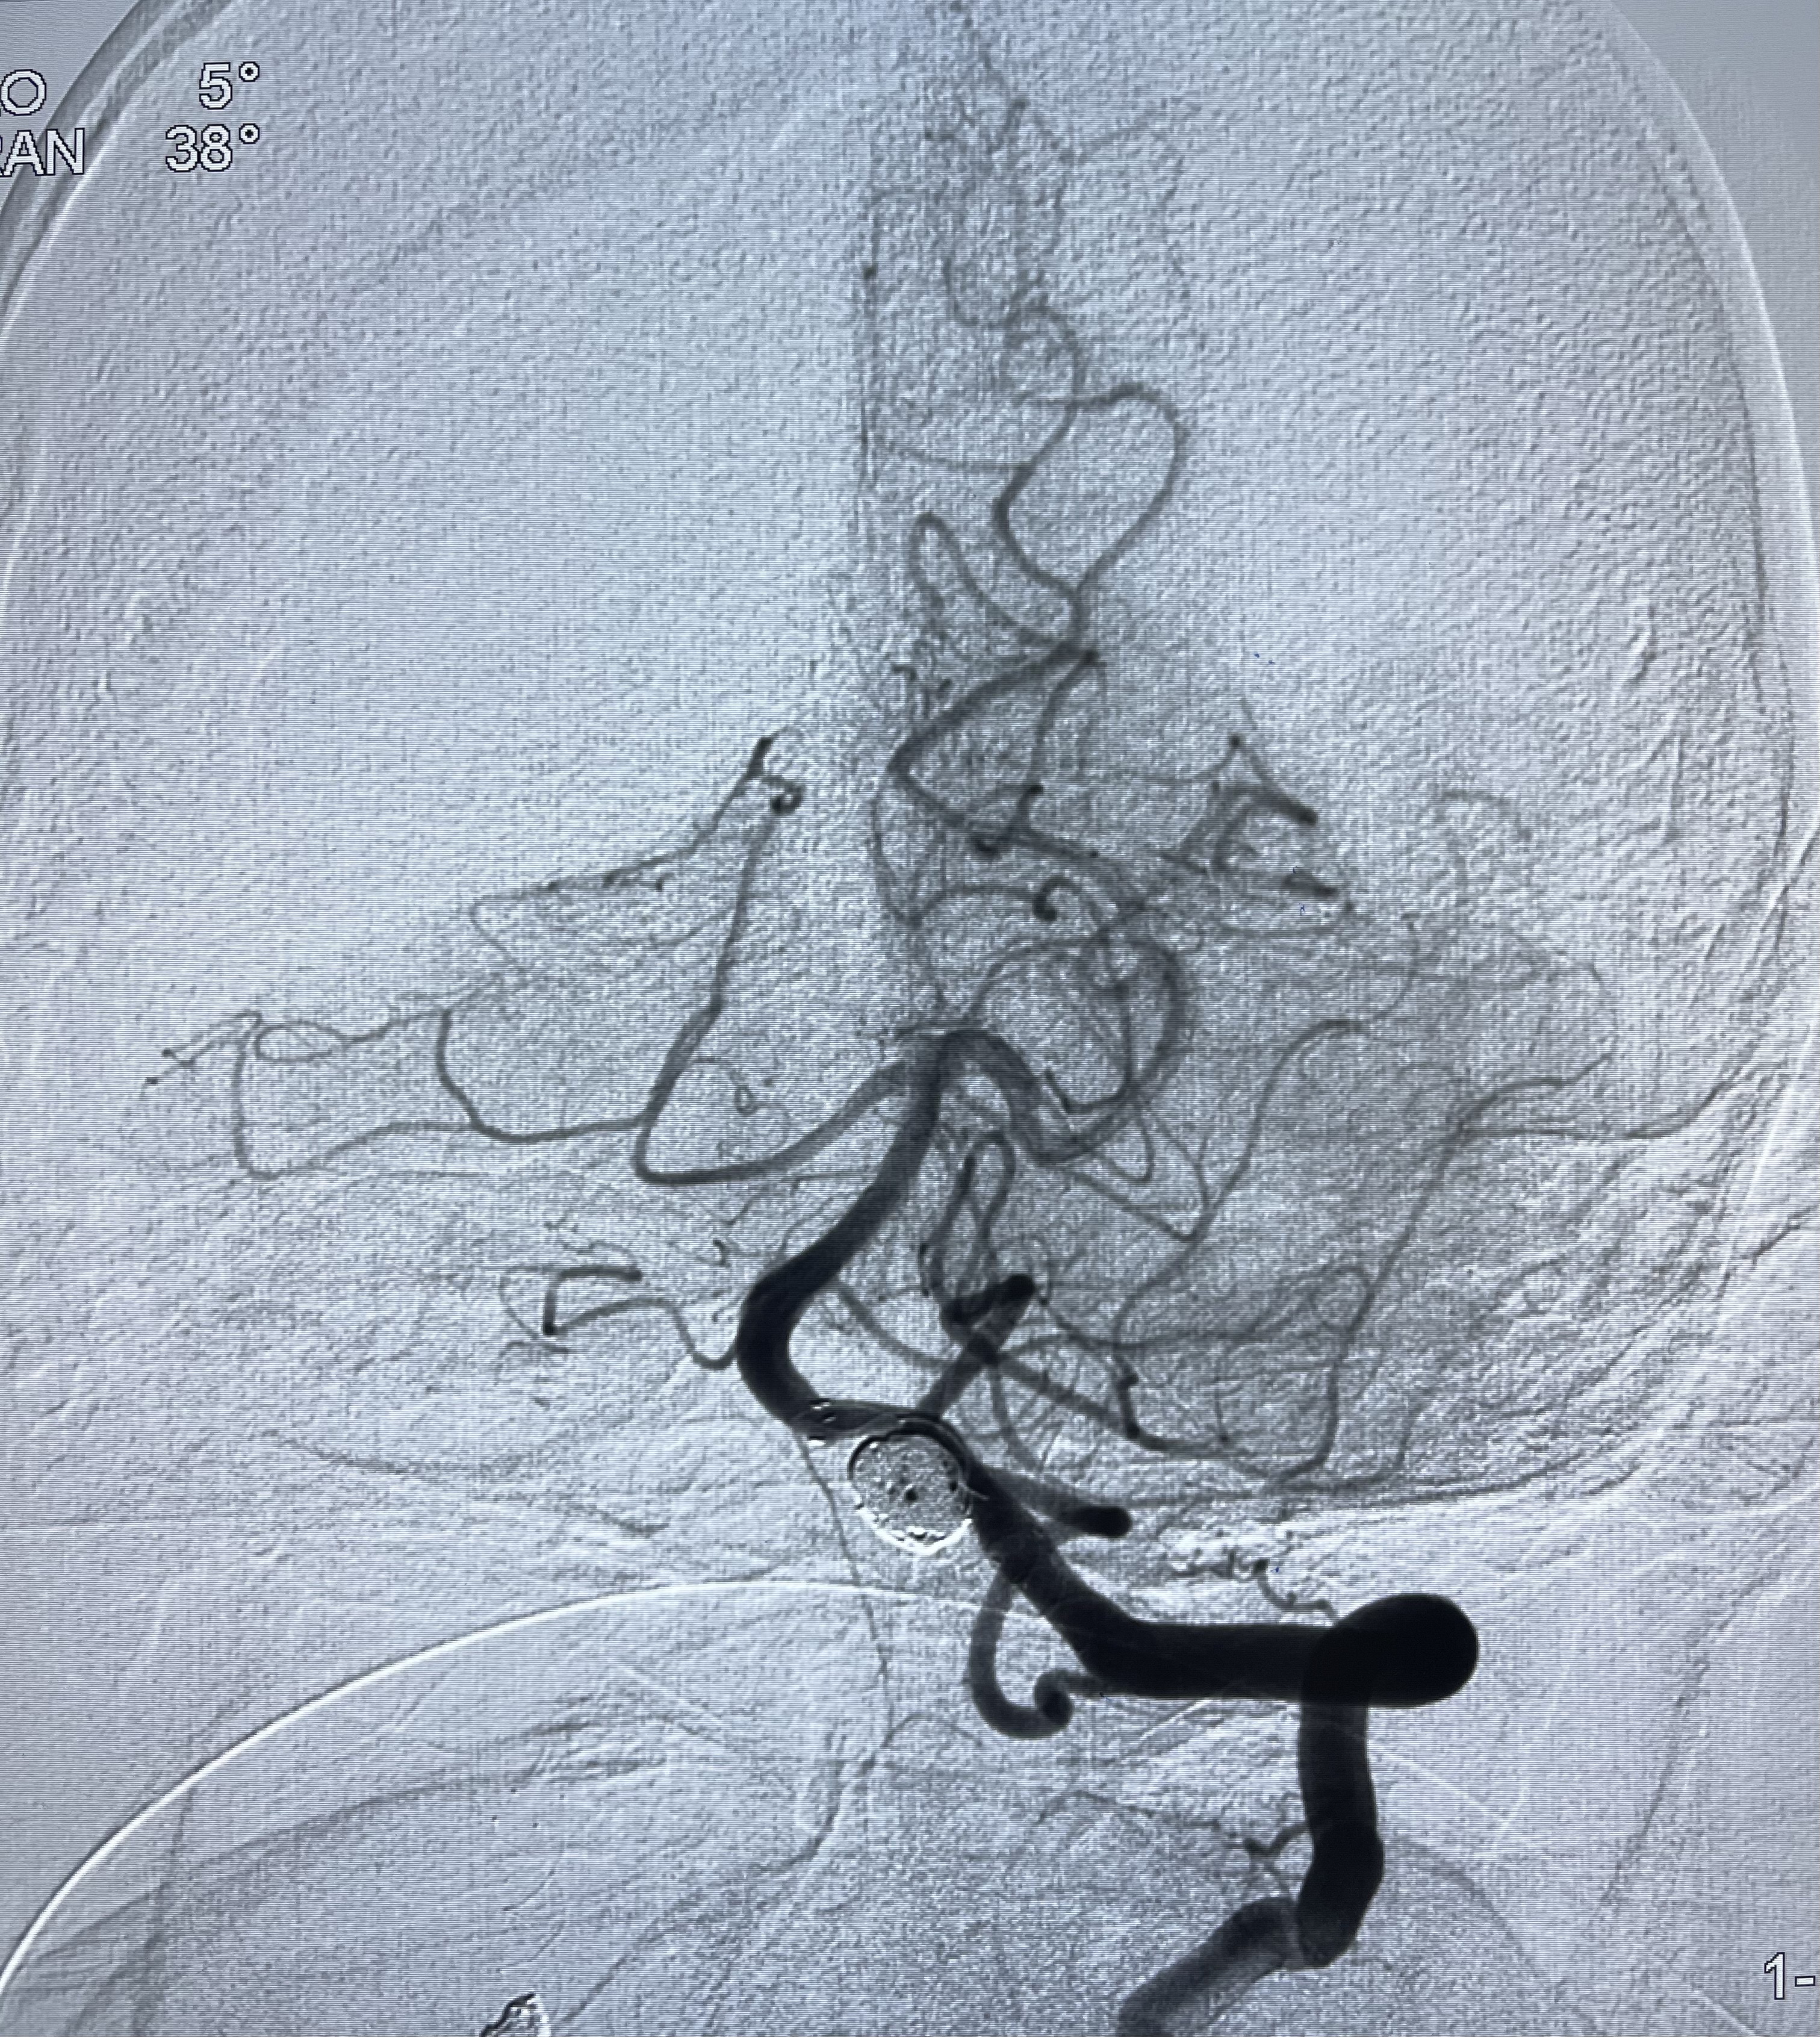

2021-03-15全麻下多发动脉瘤支架辅助栓塞

右侧颈内动脉夹层动脉瘤Lvis5.5-20mm支架辅助栓塞

左侧椎动脉V4夹层动脉瘤多支架辅助栓塞:

即刻造影